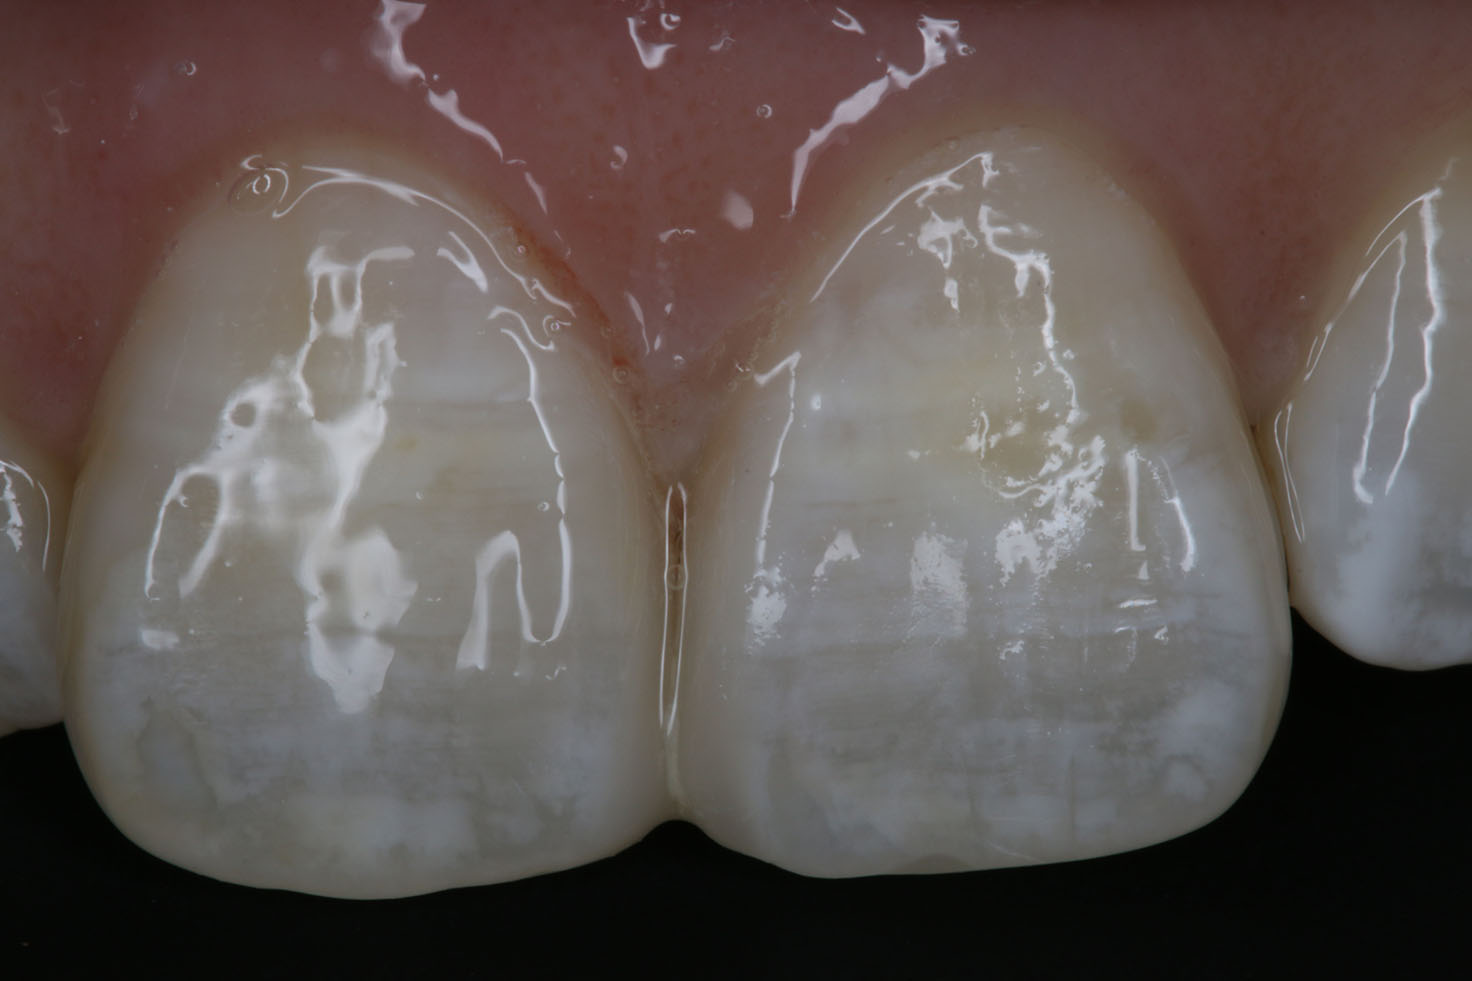

Space Closing

Aesthetic space closing without remove any of your natural tooth structure. Aesthetic, natural-looking and long-lasting result!